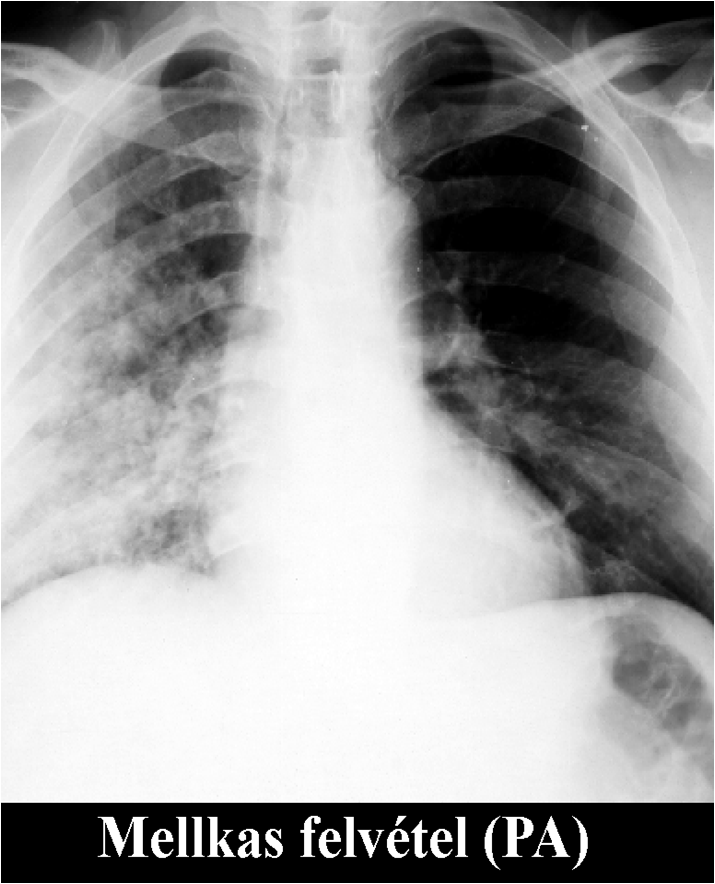

The brightness of the picture can also be altered, making too dark or too light parts of the picture assessable. The windowing allows changing of the brightness and contrast at the same time. If we change them accordingly tissues with different absorption can be highlighted. For example, low brightness and low contrast settings allows good visualization of the bone structures, but other tissues appear moderately pale. High brightness and contrast settings results in a good visualization of the lung tissue while other tissues appear bright and pale.